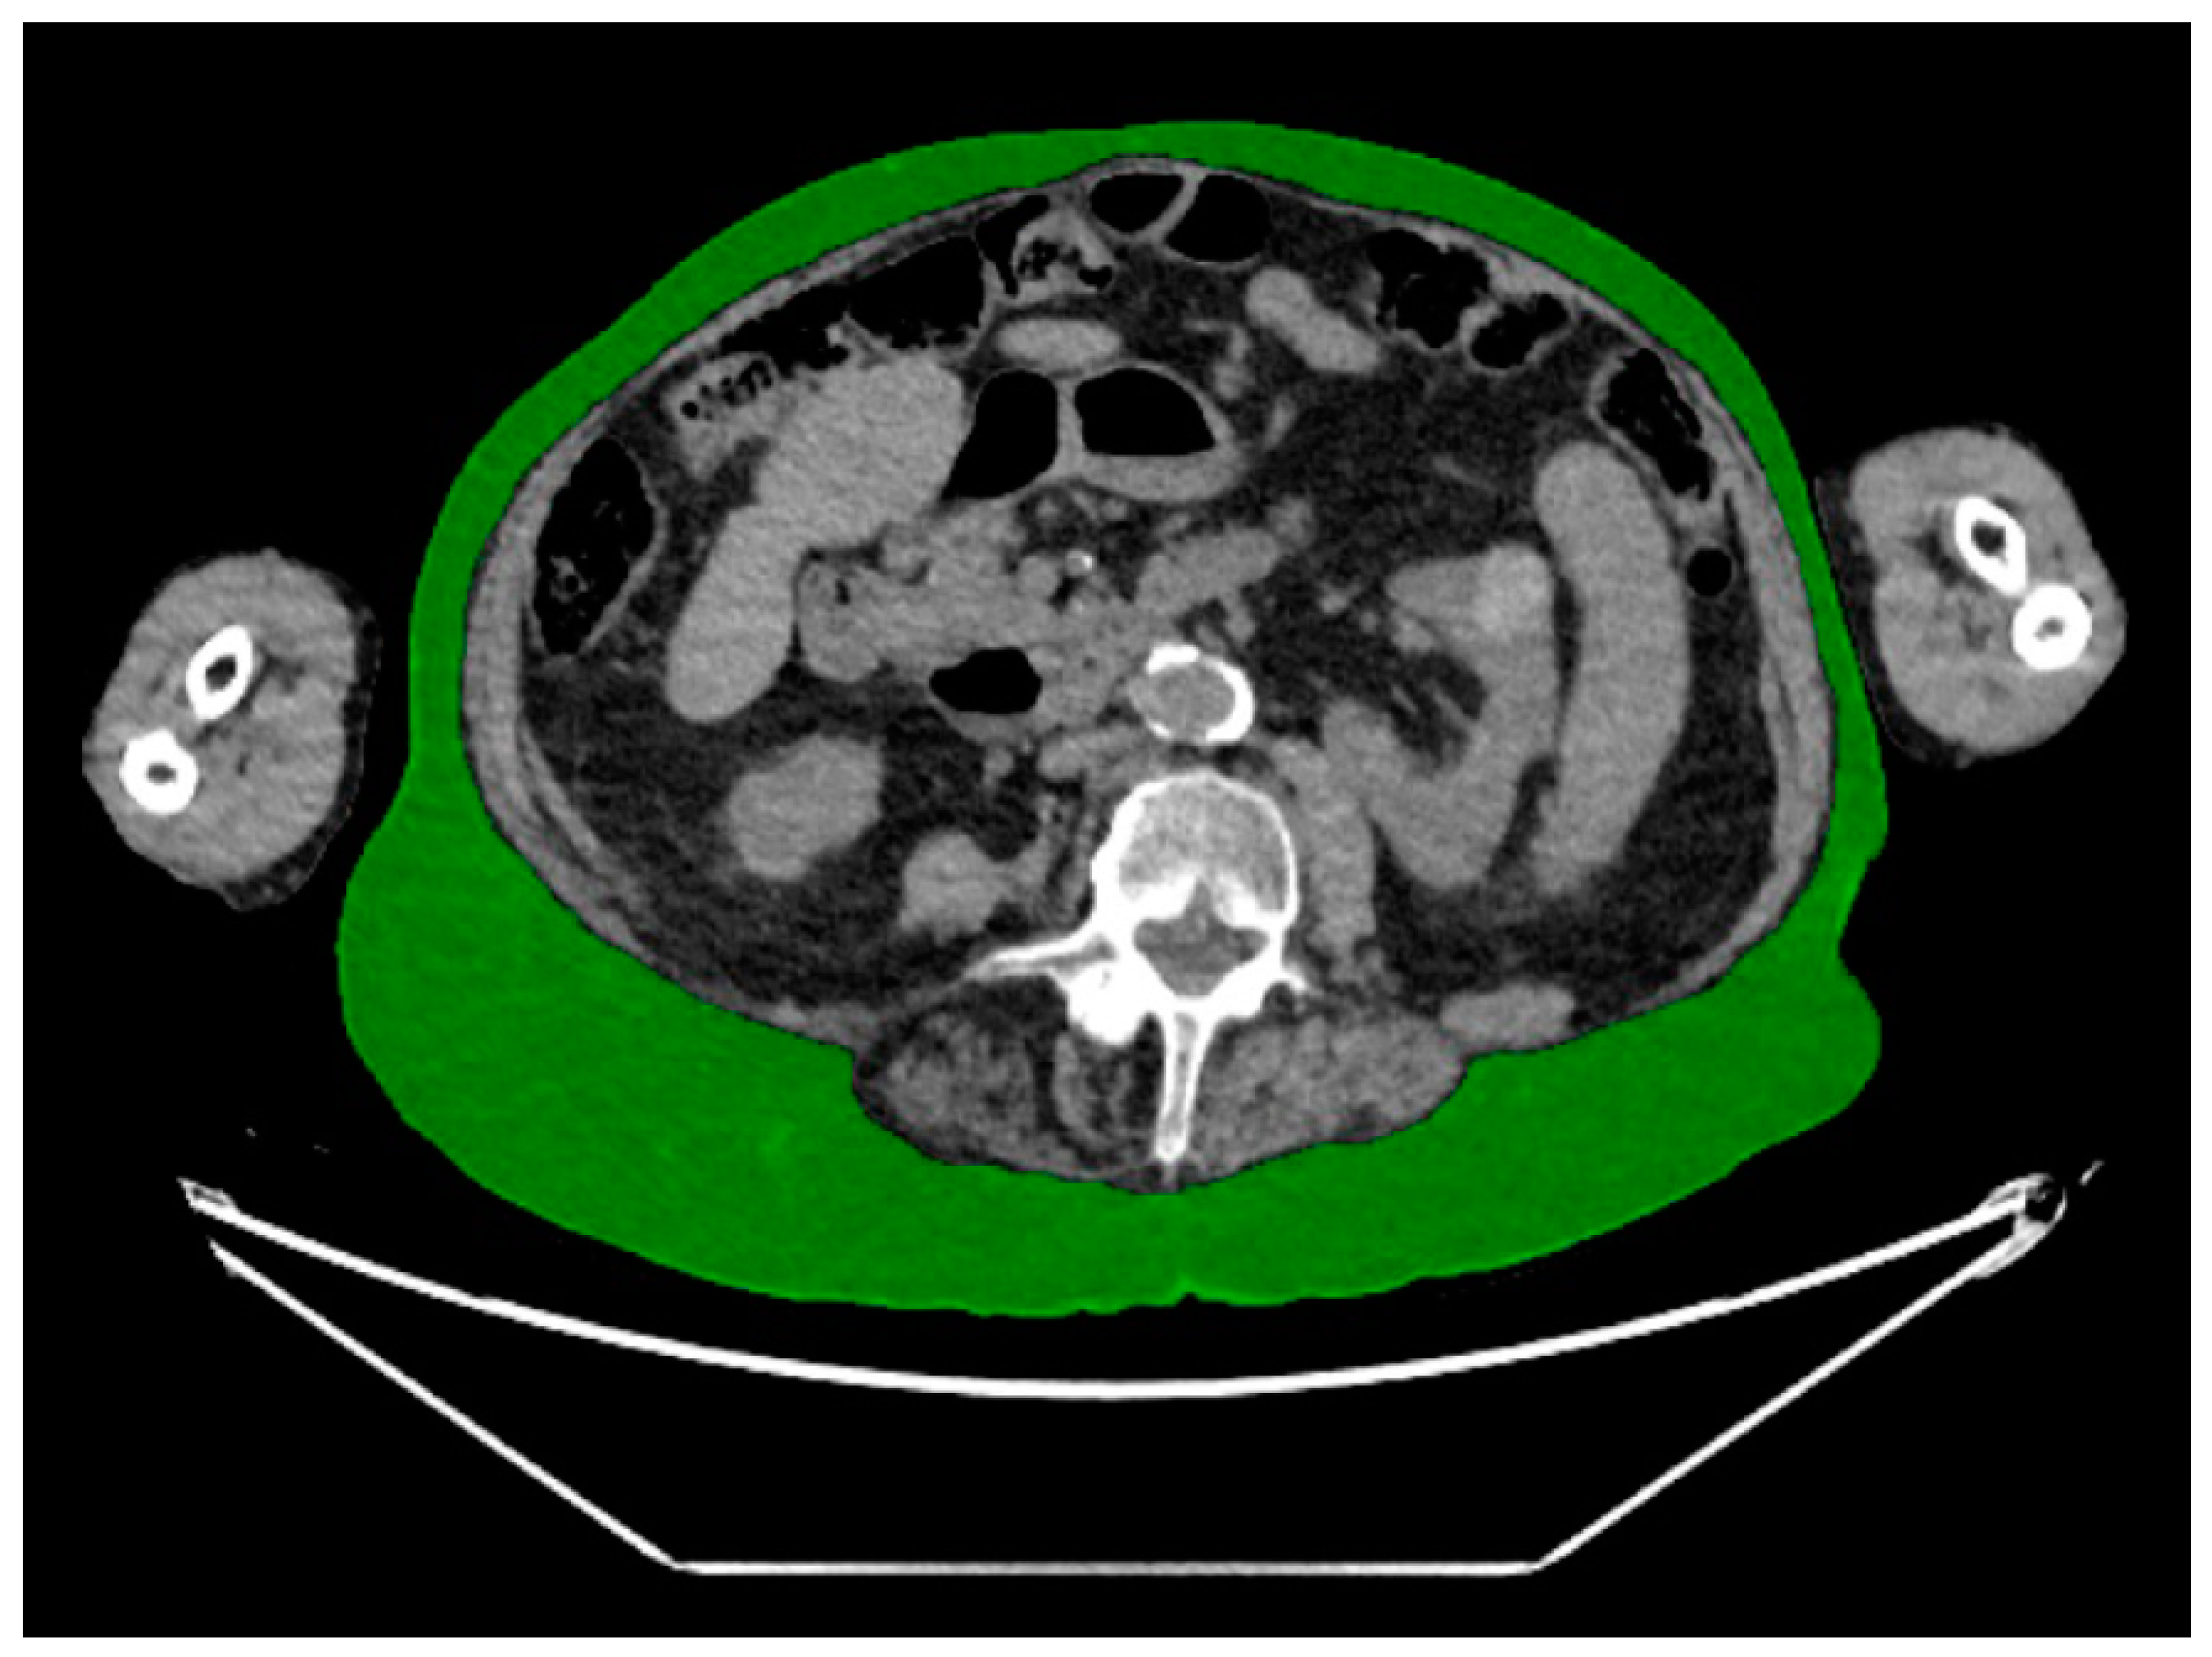

2.3. CT Body Composition Assessment

| Body composition measures a | Median (IQR) or % (n) |

| Subcutanous adipose tissue | |

| Area (cm2) | 249 (180–320) |

| Visceral adipose tissue | |

| Area (cm2) | 124 (75–211) |

| Muscle | |

| Area (cm2) | 140 (116–165) |